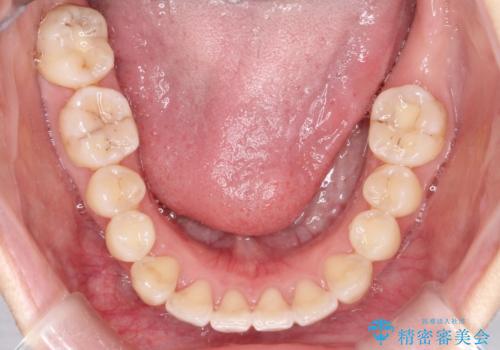

【インビザライン】前歯の凸凹をなおしたい

- 前歯の凸凹をなおしたいことを主訴にインビザラインにて矯正治療を行いました。

患者様にしっかりとインビザラインを使用して頂けたことで綺麗な仕上がりとなりました。